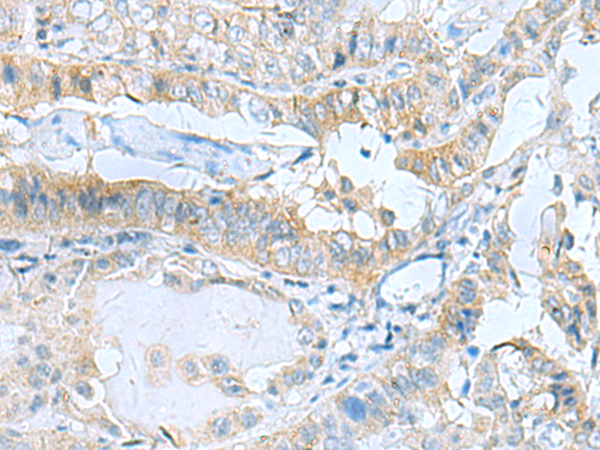

分类: 科研抗体货号: P11585别名: ASIC; ACCN2; BNaC2应用: IHC反应种属: Human, Mouse, Rat